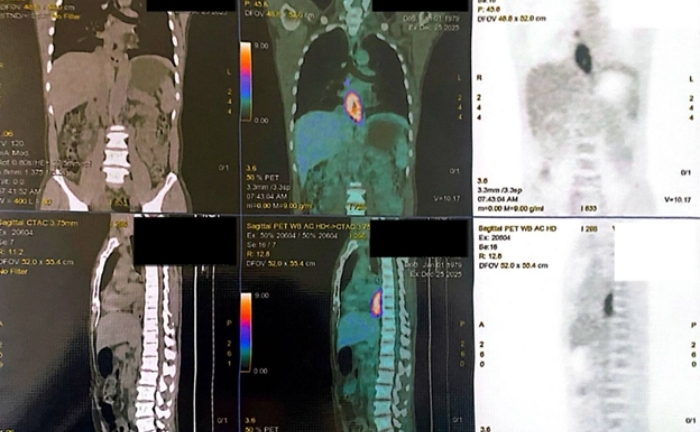

(VTC News) - Triệu chứng của bệnh ung thư này thường là cảm giác nuốt nghẹn ở cổ và triệu chứng này càng tăng dần khi các khối u ở vùng hầu họng lớn dần lên.